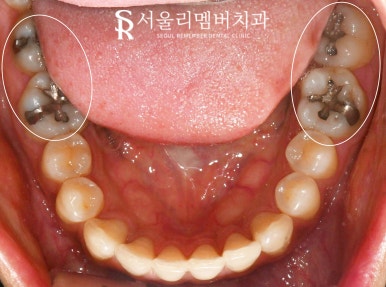

before

오늘 신림 치과 에서 보여드리는 케이스는

상하좌우 각각 2개의 큰 어금니 모두에

오래된 아말감이 존재합니다.

그래서 좌측, 우측으로 나누어

총 2회에 걸쳐 수면마취하에 교체하기로 했는데요,